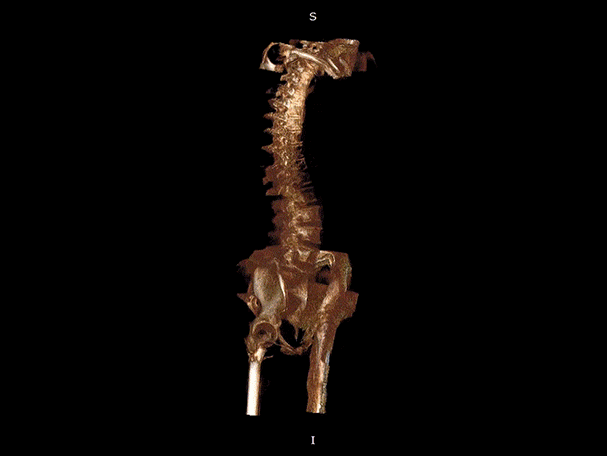

· 补位CT,提供负重位三维影像

· 引领普放走向三维精准诊断时代

填补常规CT/MR空白

助力术前规划和术后评估

VR体绘制重建